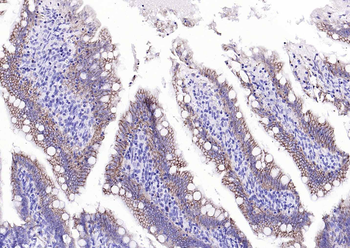

IHC-P image of human endometrial cancer tissue using anti-Emp1 (2.5 ug/ml)

Immunohistochemical staining of human endometrial cancer tissue using anti-Emp1 (2.5 ug/ml)